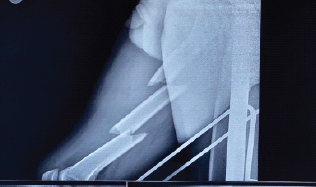

A Rare Case of Talus Neck and Open Medial Malleolus Fractures with Ankle Subluxation Treated using a Single Anteromedial Approach

S Venkatesh Kumar , Ashwath Ahila Baskar , K G Sathyendra , Ramson Vasagan , Rupali Dnyandeo Solankey , Rohini Venkatesh